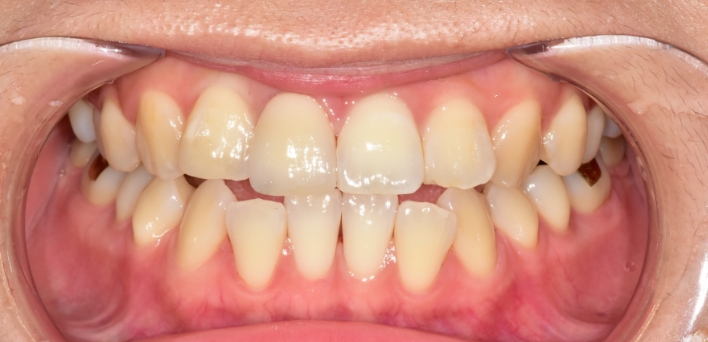

우리 얼굴에서 미소는 첫인상을 좌우합니다. 이런 좋은 인상을 위해 라미네이트를 고려 중이시라면,

많은 것들을 고려해야 합니다. 라미네이트 시 무조건 하얗고, 얇기만 한 치아가 좋은 것은 아닙니다.

개개인의 얼굴마다 비율에 맞게 이상적인 치아의 형태가 있습니다.

더서울치과의원은 정확한 안모 분석을 통한 프로파일 예측 치료로 심미성은 물론 치아 본연의 기능 회복까지 가능하도록

안면 근육과 기능, 치아 형태, 비율, 크기, 교합, 색감 등 전반적인 비율을 맞추어 본인에게 잘 맞는 치아의 형태로 복원합니다.